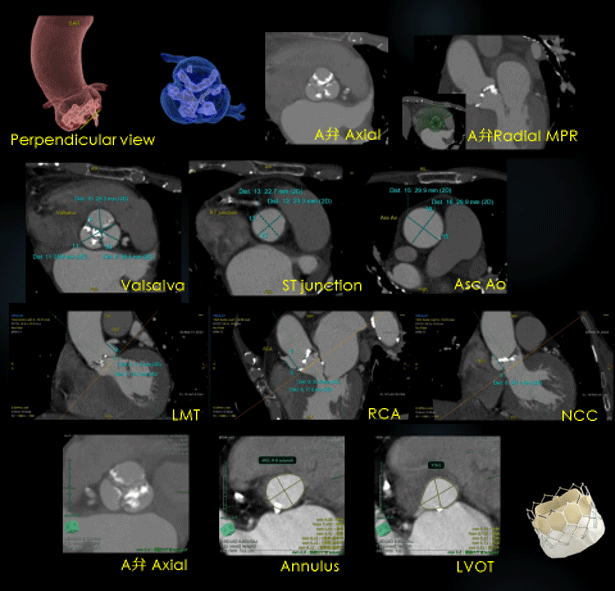

大動脈弁複合体の評価として、まず拡張期にて大動脈弁の形態、石灰化の量や分布が評価できる画像をVR、MPRで提供しています。また弁輪破裂のリスクが高い石灰化の有無の評価、冠動脈分岐部の高さ(冠動脈閉塞のリスク予測)の計測など、大動脈基部と大動脈弁の評価などを行っています。

RevolusionCT_OguraKinen_08.png

TAVIにおける弁輪径の計測およびリスク

TAVI弁には、大きく分けて2種類の弁があり、sapienシリーズは面積から算出した弁輪径を用い、Evolut Rは外周長を用いてサイズを決定しており、弁輪径の計測は弁のサイズ選択に影響を与えます。

正確な弁輪径の計測が行われていない場合のリスクとしては、自己弁輪サイズに比べ植込まれる人工弁が大きすぎる場合には弁輪破裂が生じる恐れがあり,逆にサイズが小さすぎる場合は,人工弁の脱落や弁周囲逆流の頻度が高くなることが予測されます。

RevolusionCT_OguraKinen_09.png

弁輪径計測の最適心位相とは